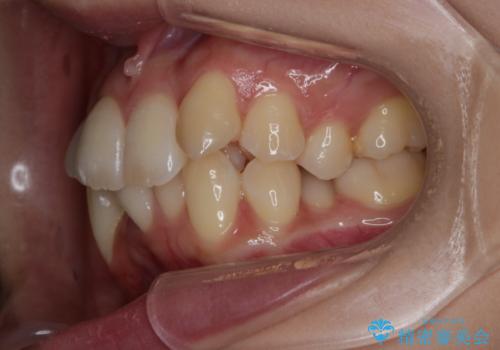

がたつきが強いガチャ歯。埋伏歯抜歯+矯正。すごいところに犬歯が埋まっていたのを抜いてワイヤー矯正治療

がたつきの強さから4本抜歯の必要性がありましたが、右上の歯は犬歯が一本埋まっており、乳歯がある状態でした。

右上については先に乳歯を抜歯して、犬歯が使えるようであれば第一小臼歯を抜歯することとして治療を開始しました。

当初、犬歯が動くようであれば代わりに小臼歯を抜歯する予定でしたが、

開窓して器具で力をかけても動く様子がなかったため抜歯とし、小臼歯を犬歯に見立てて治療を完了しました。